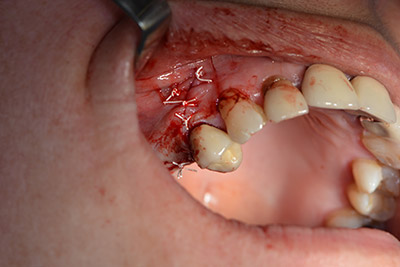

Die klassische Schnittführung (krestal, Entlastung bukkal) und das Präparieren des Mukoperiostlappens erlauben eine gute Übersicht.

In diesem Fall werden Sky Implantate (bredent) verwendet, deren chirurgisches Protokoll die Pilotbohrung mit etwa 1.200/min vorschreibt (Abb. 9).